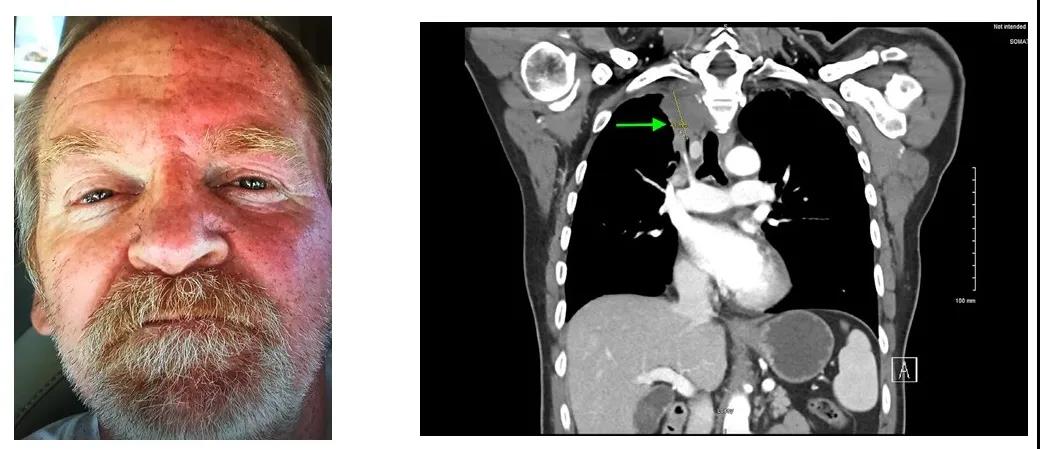

无独有偶,2020 年 Current Problems in Cancer 杂志上另一位体力劳动后仅一侧面部出汗和潮红的 59 岁男性再一次进入我们的眼球。同时患者也有右侧上睑下垂和瞳孔缩小。胸部 CT 提示「从中作梗」的同样是右肺尖的不明占位——4.1 cm 的占位性病变且延至 T2/T3 神经孔,后期活检证实为肺腺癌 [2]。